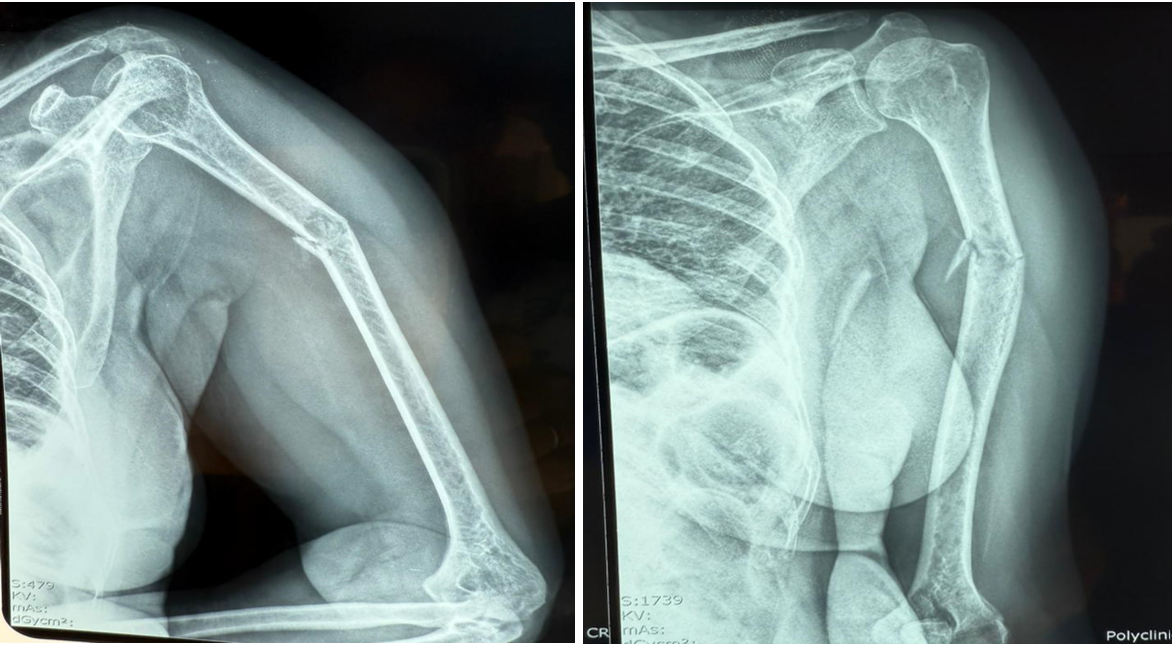

The X-ray of the left upper limb (Image 2) revealed :

- a minimally displaced fracture of the upper third of the humeral shaft with an excluded fragment

- bone demineralization of the shoulder and humerus related to osteoporosis

- narrowing of the left glenohumeral and acromioclavicular joints with osteosclerosis of the articular surfaces related to left osteoarthritis

Picture 2: The X-ray of the left upper limb.